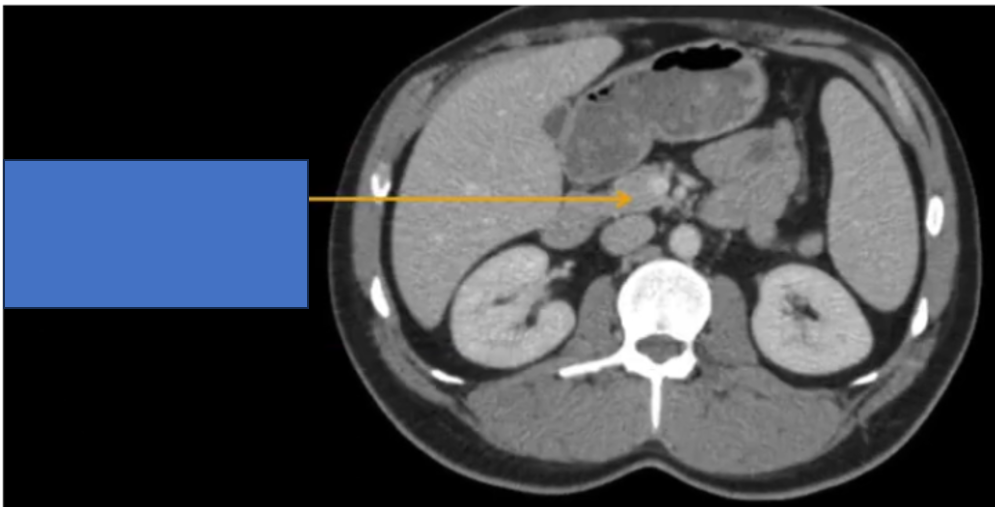

TM gan ở đâu? TM chủ dưới ? ĐM chủ?

đm thận T?